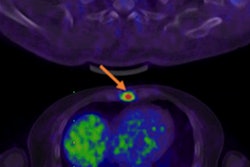

The SpaceOAR works by placing a small amount of gel between the prostate and rectum, a prostate spacer, to increase the distance between them and thus reduce the radiation dose received by the rectum during treatment.